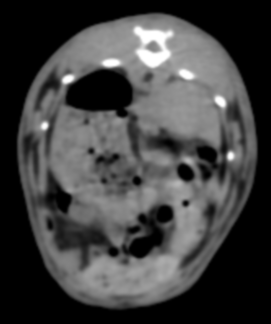

CT検査

体の内部を輪切り状に撮影し、コンピューター処理で立体画像として表示する検査です。Ⅹ線検査・超音波では見えにくい部分まで可視化できます。上記2つの検査(Ⅹ線検査・超音波)は保定(ウサギが動かないように抑えておく)必要があり、多少なりとストレスがかかってしまいます。動物のCT検査は麻酔下というイメージが多いですが、動物病院によっては無麻酔下で評価してくれる所もあります。※麻酔下と比べると精度は落ちます。ウサギはじっとしてくれることが多いので、専用のもしくは持参したケージそのままでパッと撮影可能です。Ⅹ線検査で記載したものをより細かく観察が可能になります。特にⅩ線検査ではまだわからないレベルの肺腫瘍や、歯の根尖部とその周囲組織や骨の変性の詳細な確認も可能です。胸部や腹部の詳細評価だけではなく、Ⅹ線検査や超音波では評価が難しい鼻腔内や中耳も同時に評価できることもメリットです。